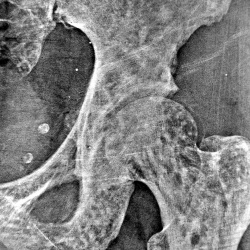

Занимался легкой атлетикой, грубых травм не было, около года беспокоят боли по внутренней поверхности бедра. Ваше мнение?